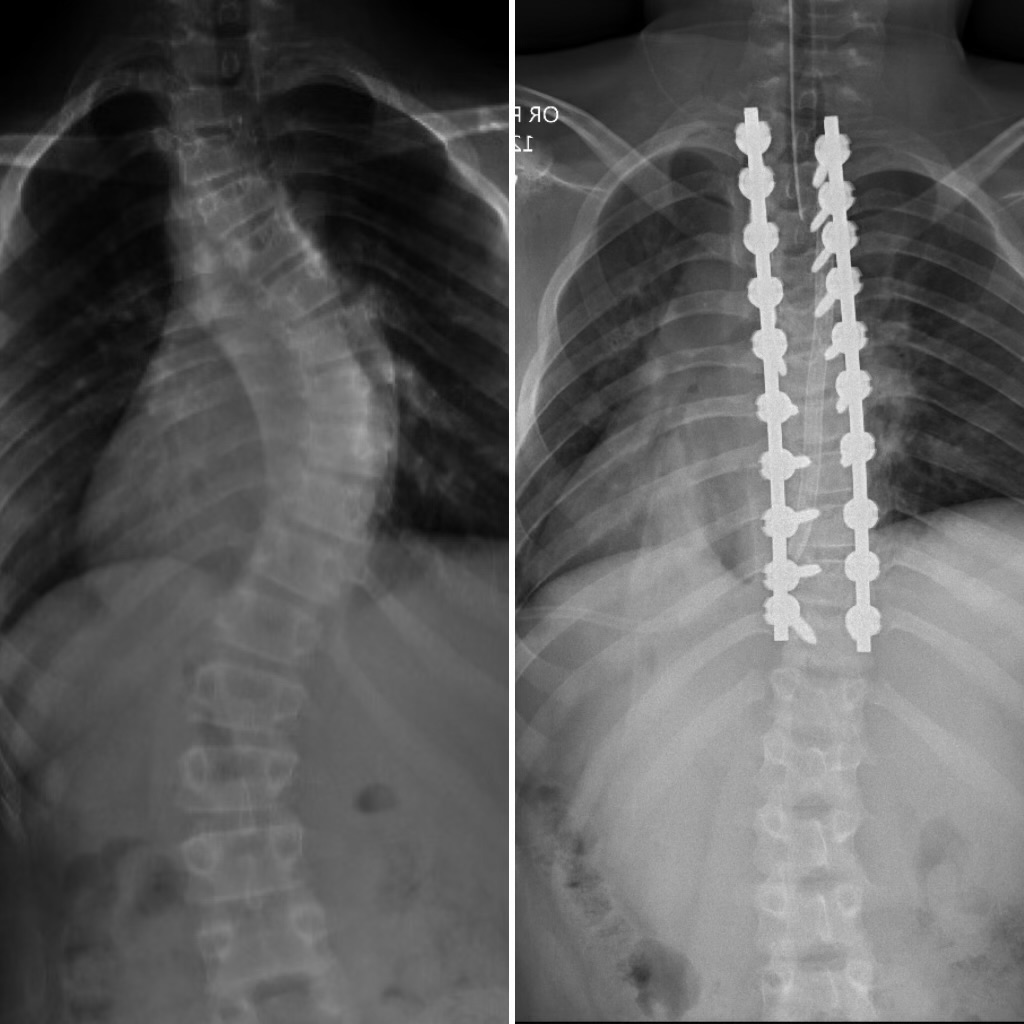

Multiple appointments and two braces later, I encountered a very large fork in the road. It appeared that the braces weren’t sufficient and I would need spinal fusion surgery. As the surgeon explained the surgery, all I heard was “titanium rods, general anesthesia, blood loss, and difficult recovery.”

Thankfully, I had an extremely renowned surgeon and a team of excellent nurses. Although the medical support was unmatched, I’m not going to act like the surgery and recovery weren’t tough. The constant beeping of my IVs and continuous awakening from my nurses prevented any slight comfort in my time at the hospital. A core memory during this period was having to relearn how to walk the day after surgery. It felt so strange. I felt like a robot perhaps because I had robot parts in me now. I looked forward to being discharged home, but my recovery at home was even tougher once the medications wore off.